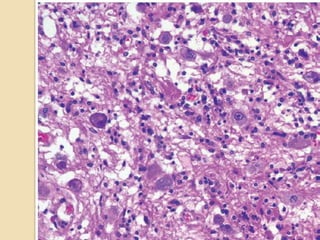

Heterogenous glial and

globoid neurons in a

conspicuous stroma

Poorly differentiated

neuroepithelial component

Histopathology

1. Desmoplastic leptomeningeal component:

•Fibroblast-like spindle-shaped cells arranged

in fascicles/storiform/whorled pattern.

•Reticulin positive network surrounds every

cell.

•Tumour cells- Astrocytes + neoplastic neurons

(atypical ganglionic cells to small polygonal

cells)

2. Poorly differentiated neuroepithelial

component: Cells with small, round, deeply

basophilic nuclei and minimal perikarya.